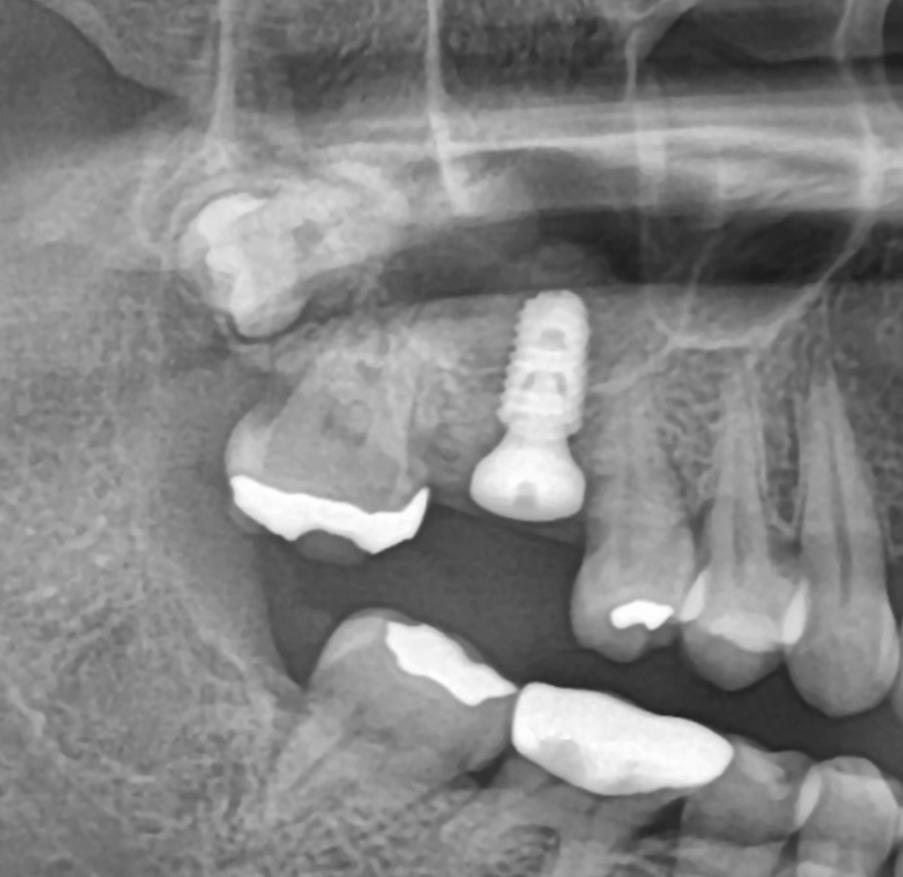

수술 후 파노라마 – 임플란트가 안정적으로 자리잡은 모습

수술 후 CT – 상악동 뼈가 안전하게 거상된 모습